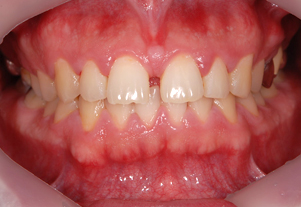

歯周病治療

しっかりと治療を行い、

健全な歯肉を取り戻しましょう。

歯周病は進行すればするほど治療が難しく費用もかかってしまいます。もちろん歯周病にならないように日々のケアをすることはとても大切ですが、万が一歯周病が進行してしまった際も、できる限り早めの処置で歯を抜かなくて済む場合もございます。

まずは当院にご相談ください。

症例1

Before

After

- POINT

- 20代前半の患者様です。年齢が若くても歯周病、歯肉炎は発症してしまいます。ホームケアの指導と治療の説明をしっかり行い、専門家によって丁寧に歯石を除去することで、健康な歯茎を取り戻しました。前歯の厚い歯茎は歯茎の形態を整える手術をしています。すべて保険治療です。